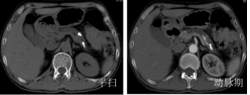

(2)腺癌CT表现:胰腺局部增大、肿块形成,多呈等或稍低密度,增强扫描多呈低密度而显示更清楚;胰头Ca常伴胰体尾萎缩;胰腺钩突变为隆凸或球形,提示钩突肿瘤;胰管和胆管扩张。

胰腺癌MRI表现:横断面所见与CT相同。T1WI肿瘤呈低或等信号,T2WI肿瘤呈稍高信号;MRCP能清晰显示梗阻扩张的胰管和胆管。

4胰岛细胞瘤:多数肿瘤较小,增强CT富血供,动脉期强化明显高于正常胰腺组织,但静脉期肿瘤密度与正常胰腺组织接近。